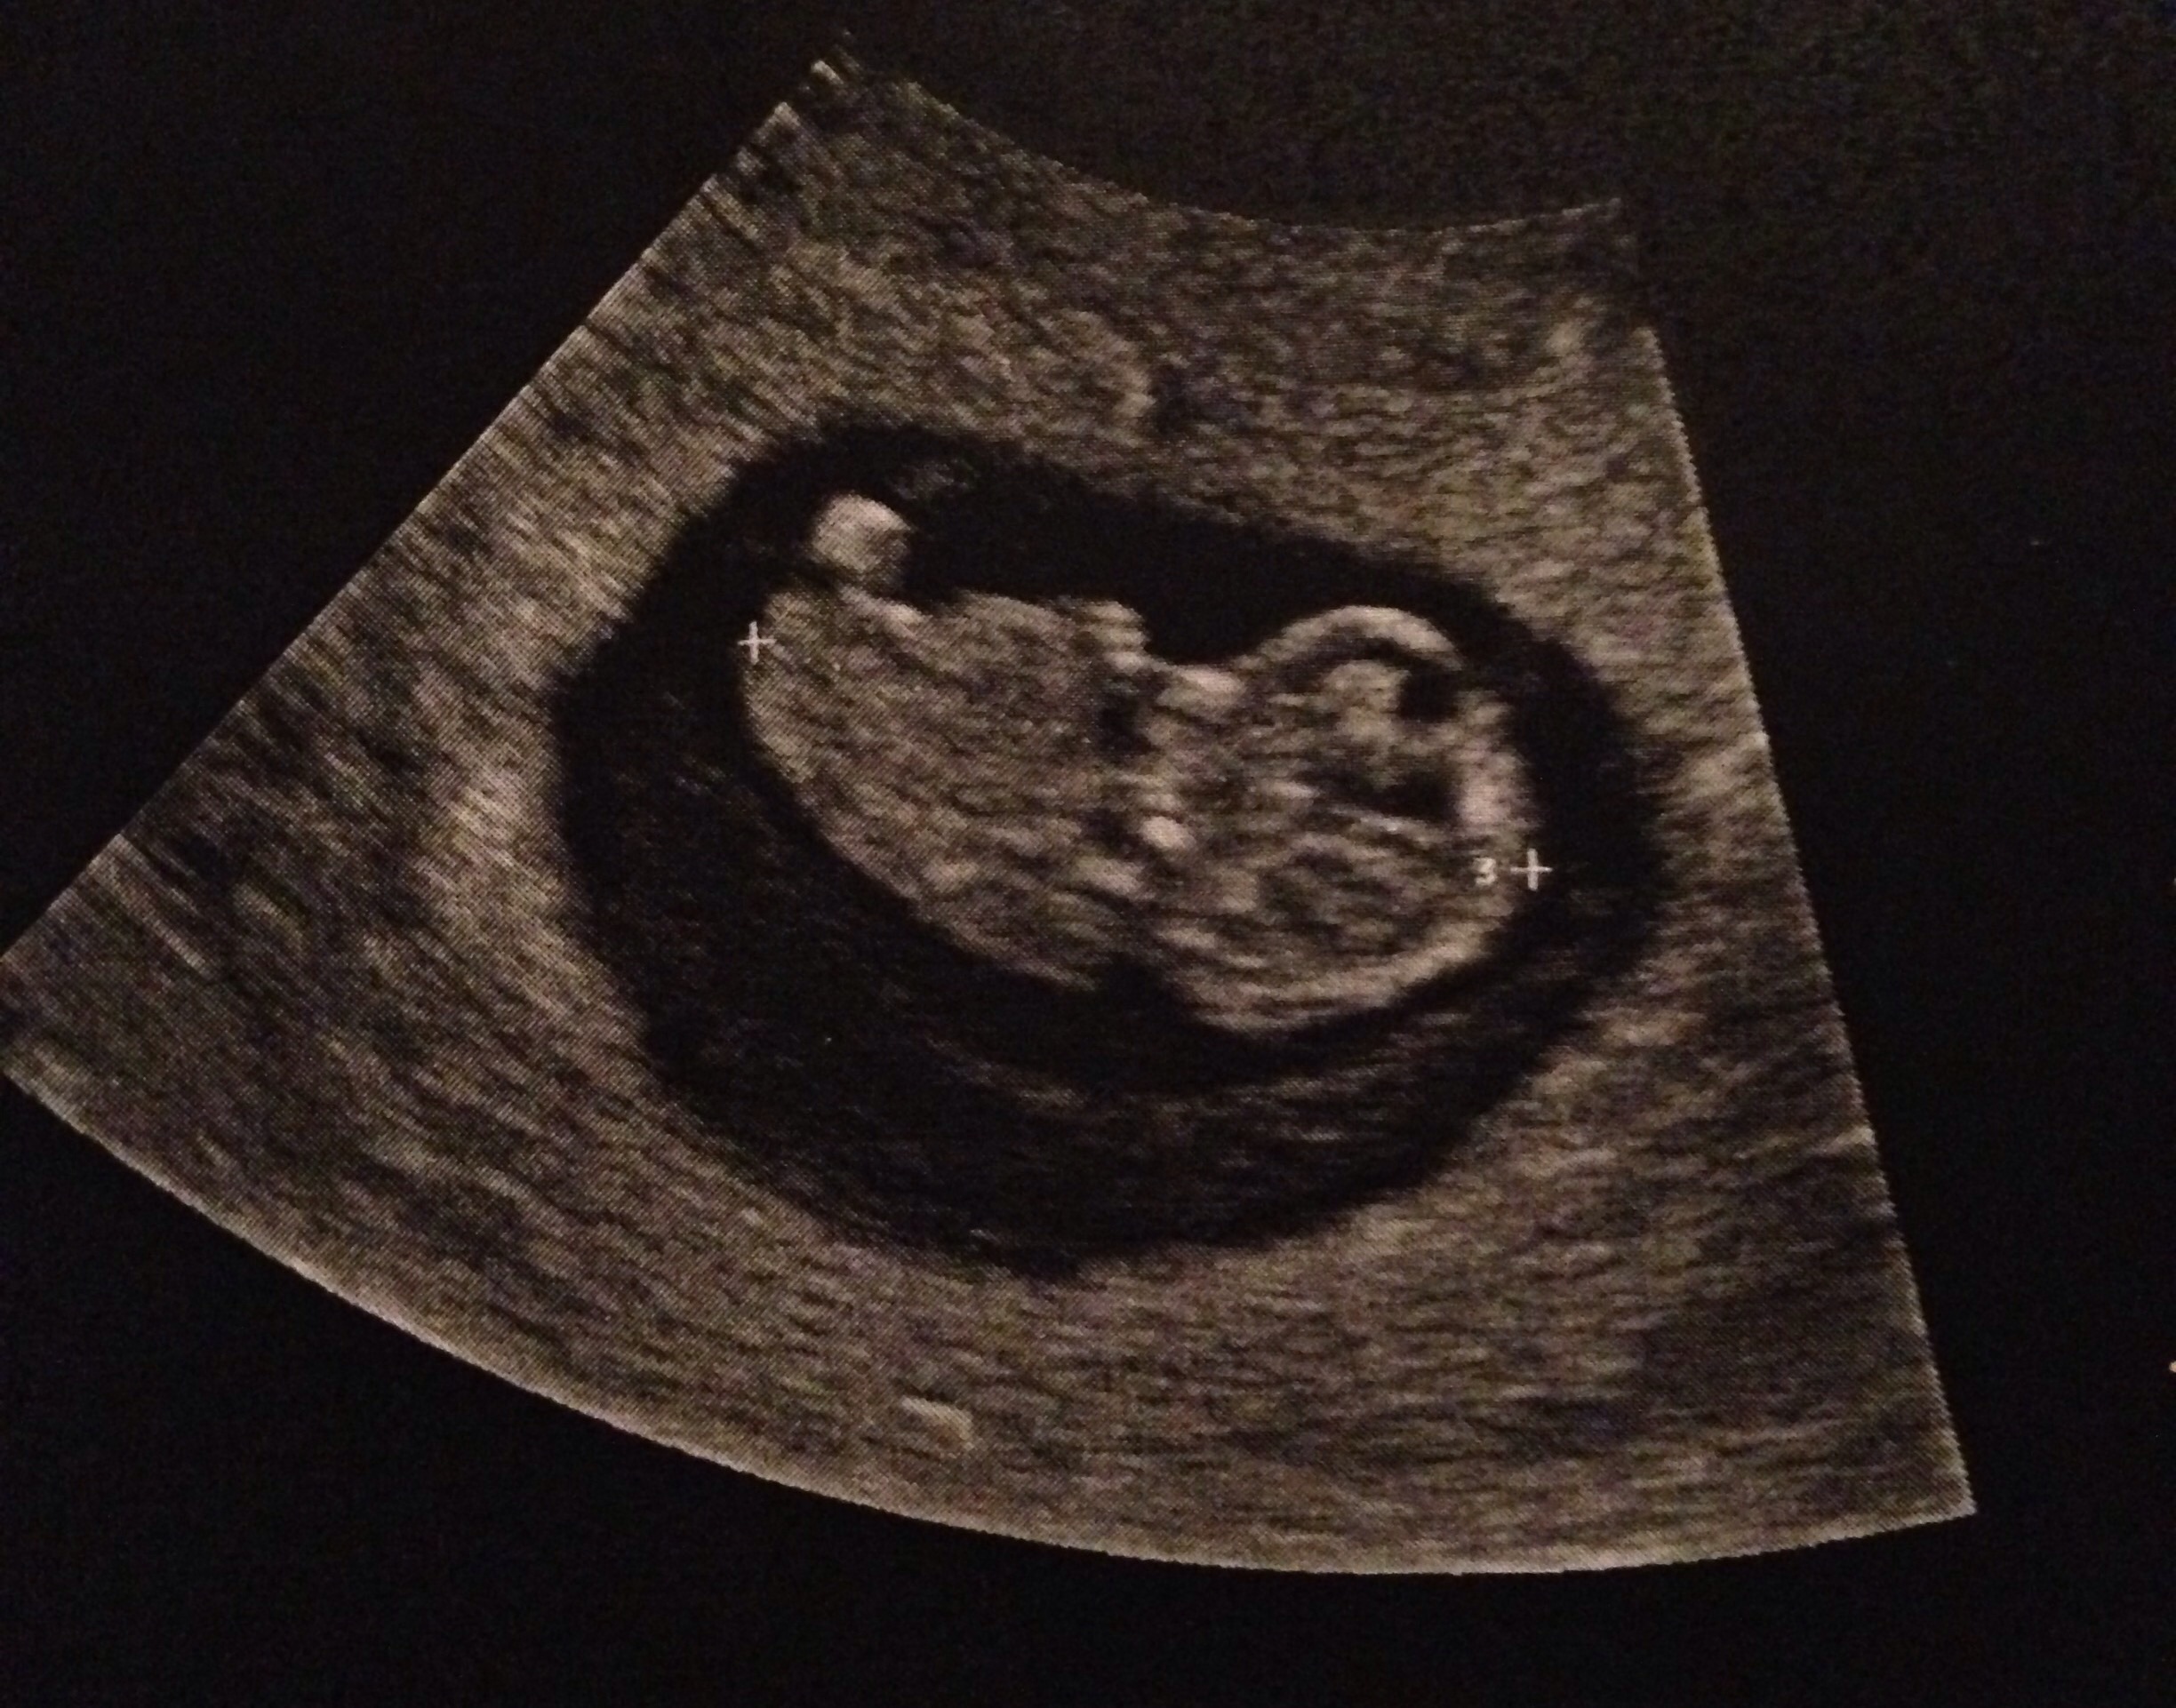

FTM! So excited to see how much my little gummy bear has grown in two weeks! 1st pic is at 6w5d, HR 147, and just a little blob with a flickering heart. 2nd & 3rd pics are at 8w5d, HR 176, and looked so much like a tiny baby with bitty arms and legs. Doc says baby is healthy and quite a dancer, it was moving and waiving all over the place. What a blessed moment to see!